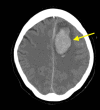

Cerebrovascular pseudoaneurysm development and rupture is a rare, delayed sequelae of trauma. We present a case of a female patient in her sixties who presented after a fall without evidence of vascular injury on imaging. However, after one week, repeat imaging due to an abrupt change in mental status revealed a ruptured pseudoaneurysm, which was treated with a combination of coil embolization and open surgical evacuation of associated intracranial hematoma. This case illustrates the importance of continued surveillance beyond the acute traumatic period to identify late-onset complications in trauma patients requiring emergent treatment.